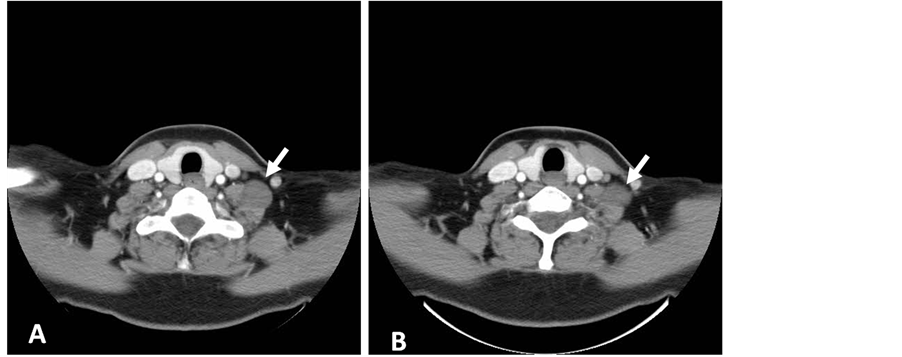

A 42-year-old lady presented with a left neck progressively enlarging swelling for three months duration. There was no history of trauma, pain, hoarseness, dysphagia, syncopal attacks or any constitutional symptoms. Systemic physical examination was normal, however locally; there were a 2 × 2 cm firm, nonpulsatile and fairly mobile mass located at the left mid-cervical region. It was not tender, warm or fluctuant and clinically resembled an anterior cervical lymphadenopathy. Otoscopic and oropharynx examination as well as indirect laryngoscopy revealed no abnormality or any source of infection. She was neurologically intact with no evidence of sensory loss and myotomal weakness or abnormal reflexes. Blood investigations showed normal values. A computed tomography (CT) of the neck was performed and discovered a well-defined mass in left lateral cervical region measuring 2 × 2 cm at the level of fourth to fifth cervical vertebra (Figure 1). A fine-needle aspiration was performed, which was inconclusive.

Figure 1. Contrast enhanced computed tomography (CT) scan (axial view) showing the isodense lesion in left cervical region with minimal enhancement (white arrows).